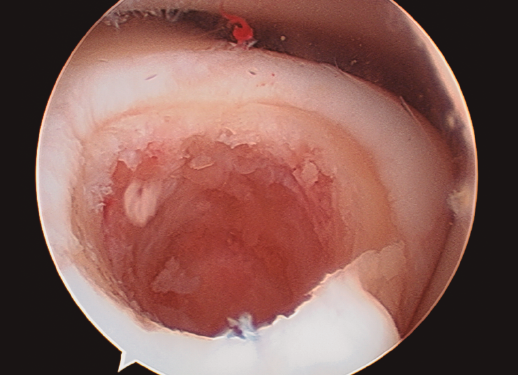

Figura 4. Aspecto final de la membrana de colágeno tapizando completamente el lecho de la lesión.

- Finalmente, procedemos a la colocación de la membrana previa fijación con Tissucol Duo® (sistema adhesivo de fibrina de 2 componentes congelado, tratado por vapor) (Figura 4) y esperaremos 10 minutos hasta comenzar la movilidad del tobillo y comprobar su estabilidad y la ausencia de pinzamiento de la misma.